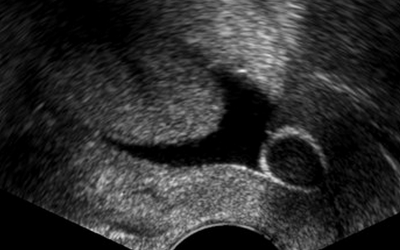

Hystérosonographie, hystéroscopie, la fin du Gold Standard ?

Source : Hum Reprod Update. 2015 ; 21(2):262-74

Dr Géraldine Porcu-Buisson Institut de Médecine de la Reproduction - Marseille

L’hystérosonographie est une méthode non invasive de bonne valeur diagnostique qui évalue en 2D (ou 3D) la cavité utérine après l’injection de sérum physiologique. Cette technique n’est cependant pas utilisée en pratique courante et en première intention dans le bilan initial d’un couple infertile alors que de nombreuses études ont rapporté sa capacité diagnostique.